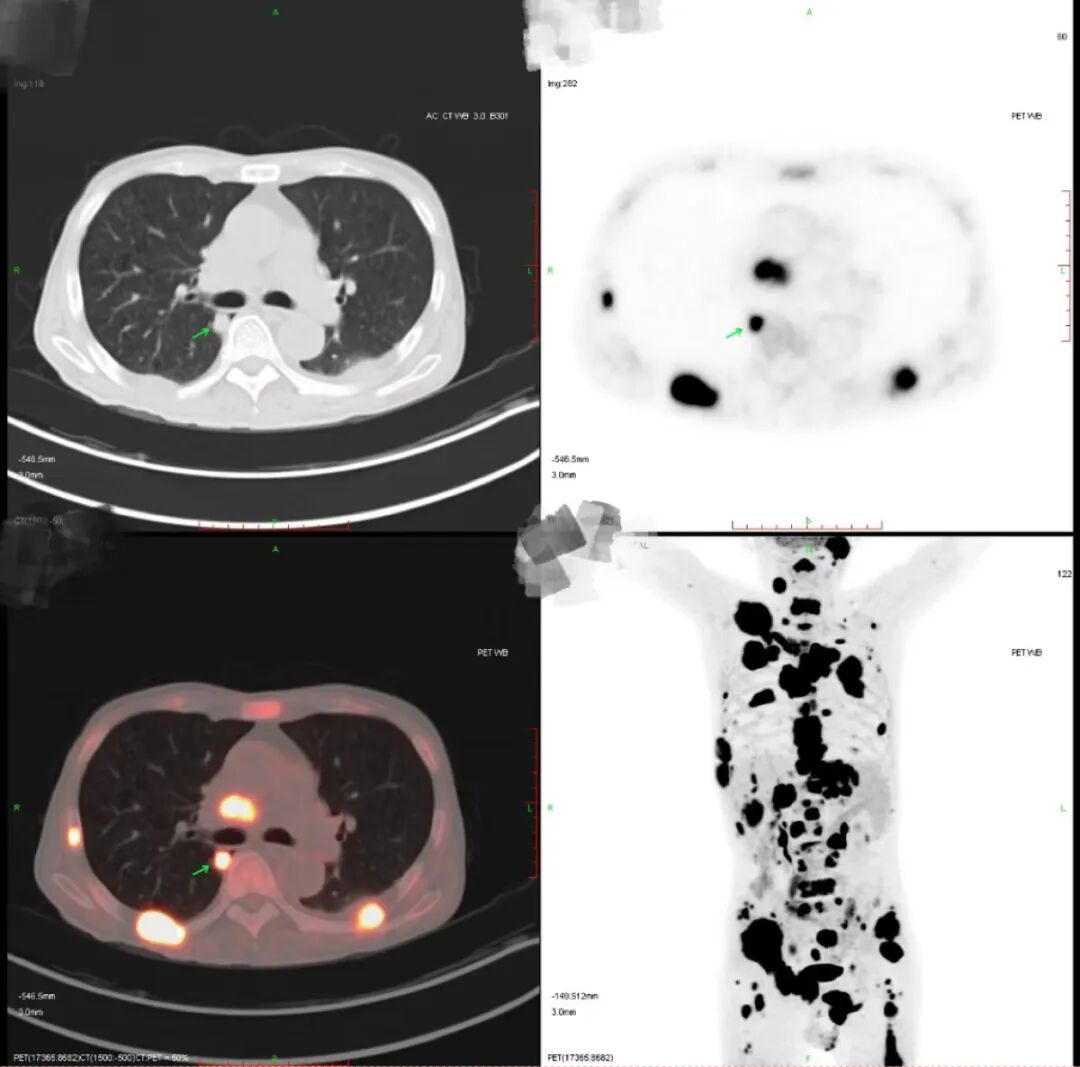

(PET-CT提示右肺上叶恶性病变可能,

且伴有全身多发转移)

孙旭迅速为他安排了PET-CT,结果在右肺上叶发现了一个小于1公分的病灶。

谜团解开了,闫先生确诊为肺癌晚期,且伴有多处转移。医生们的努力终于找到了真凶,这起“悬案”就此告破!

确诊后,下一步就是为闫先生制定精准的靶向治疗方案。幸运的是,检测显示闫先生具有EGFR基因突变,这为他的治疗提供了靶向药物的支持。